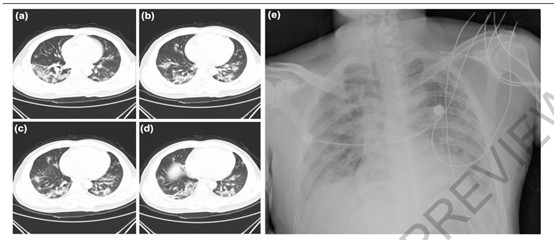

其于2019年12月26日在武汉一家医院住院,表现出呼吸系统疾病症状,包括发烧、胸闷和咳嗽。联合使用抗生素、抗病毒药和糖皮质激素进行治疗,但患者表现出呼吸衰竭,治疗三天后病情无改善。

两篇新冠病毒论文解析来自华南海鲜市场的病例707 / 作者:UFO爱好者 / 帖子ID:82804

该例病人发病6天后,左肺可见明显病灶。